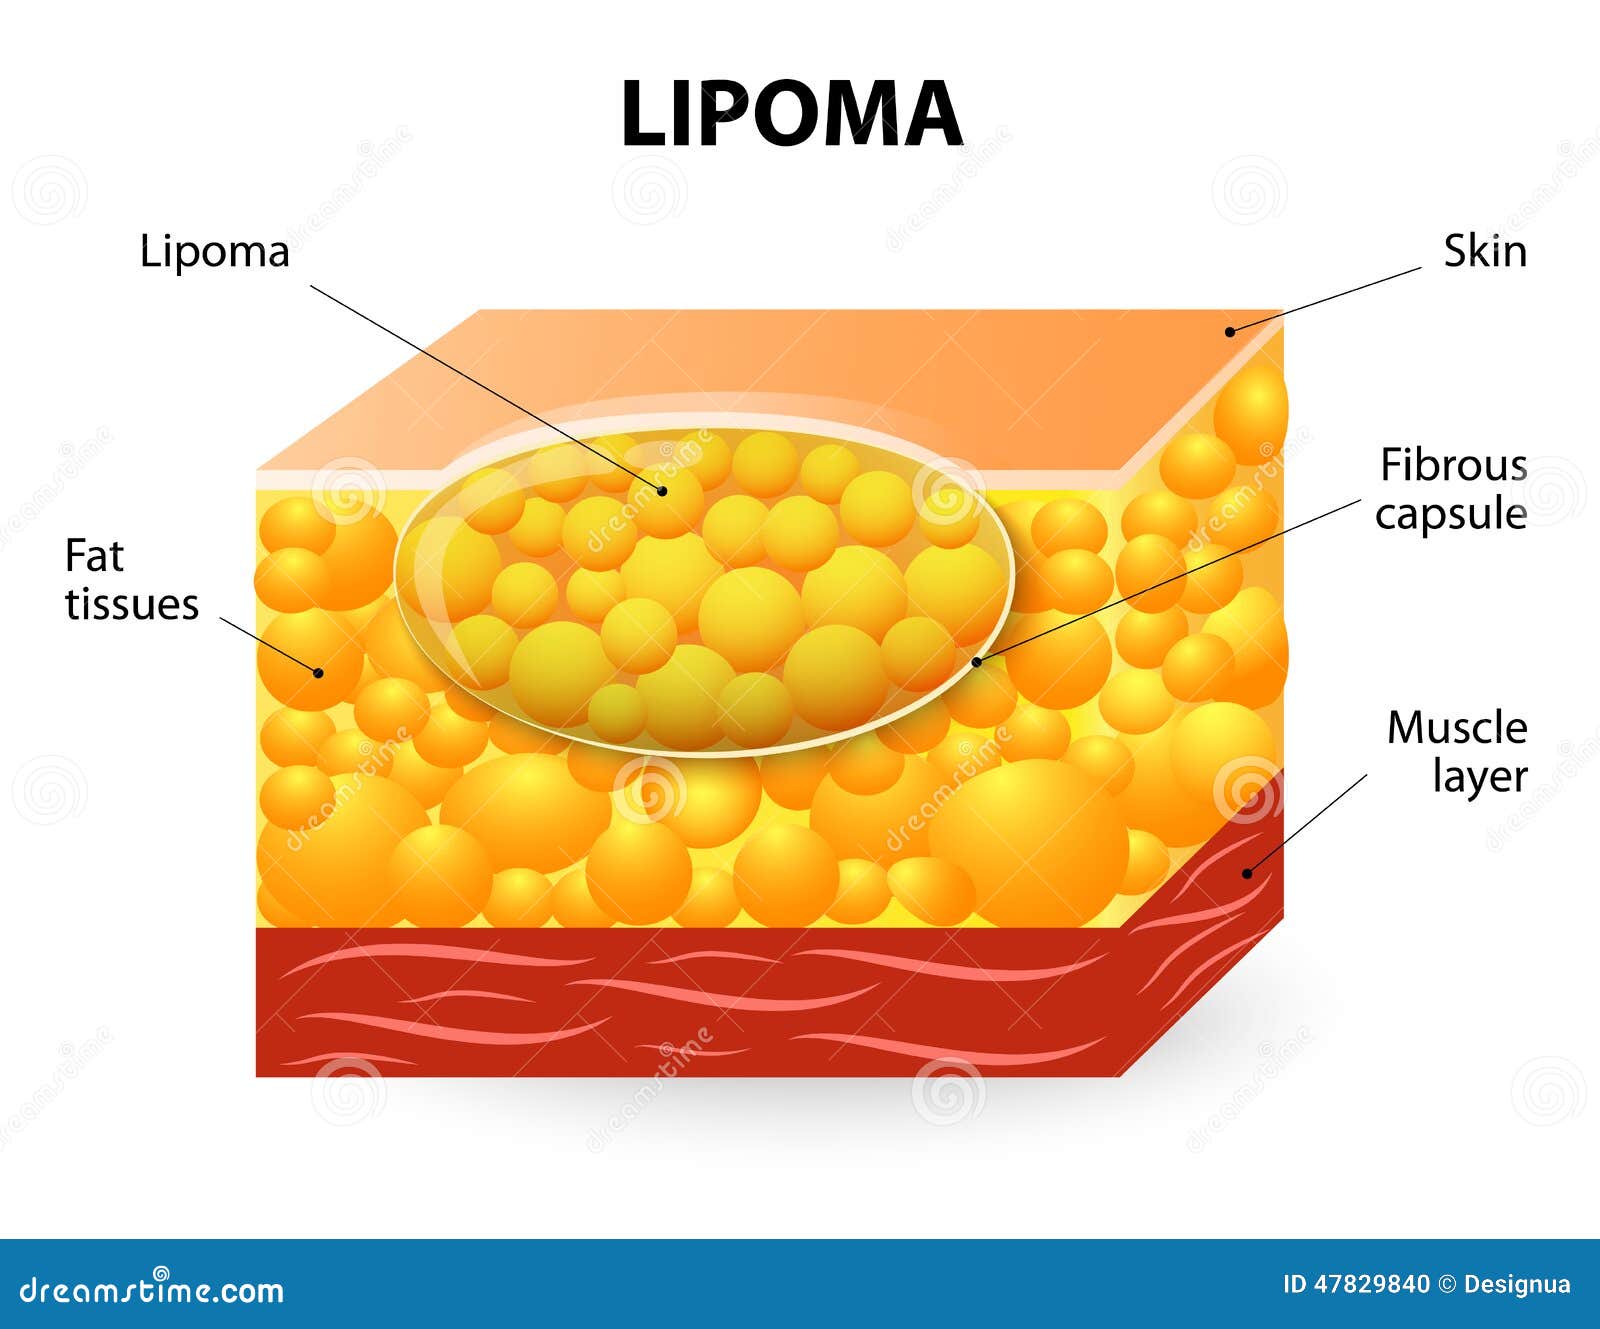

Lipoma stock vector. Illustration of stitches, science – 47829840